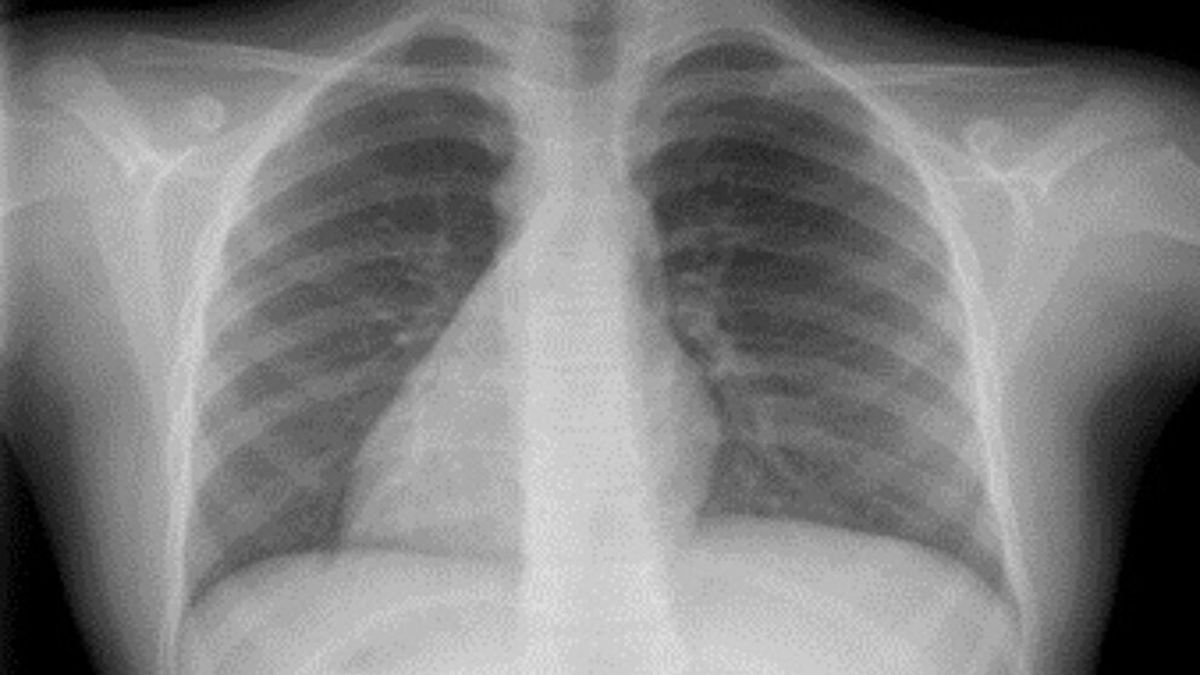

Por más increíble que parezca, lo cierto es que hay algunas personas que tienen el corazón en el lado derecho de su pecho. Esta extraña anomalía congénita se denomina situs inversus, donde los órganos torácicos y abdominales están posicionados en el lado opuesto de lo normal.

En concreto, los órganos del cuerpo que se encuentran invertidos bajo esta condición son el corazón, los pulmones, el hígado, el estómago, el bazo y la esícula biliar.